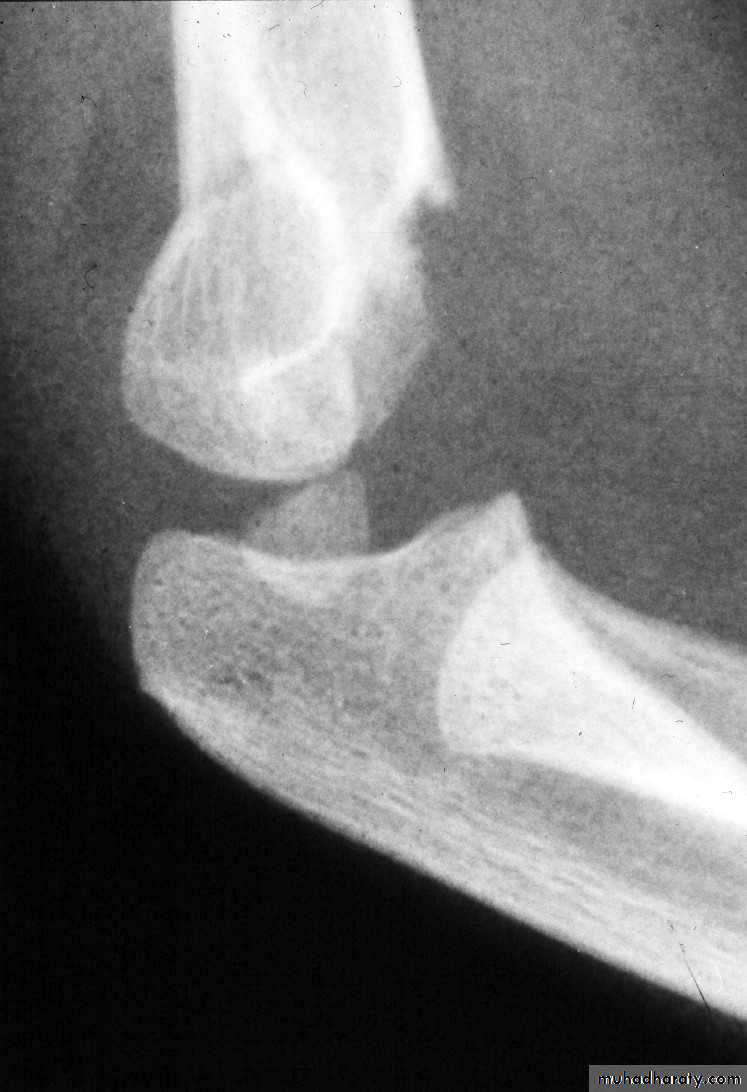

This fracture

was irreducibleby closed

manipulation.

Injury film

The posterior

tricepssplitting

approach

Advantages:

Easy approach

Direct

visualization

of fracture site

Disadvantages:

Injures virgin

tissue

Unable to

visualize

anterior A. & N.

*Compliments of Jamie Maclean(Pearth ,Scotland)